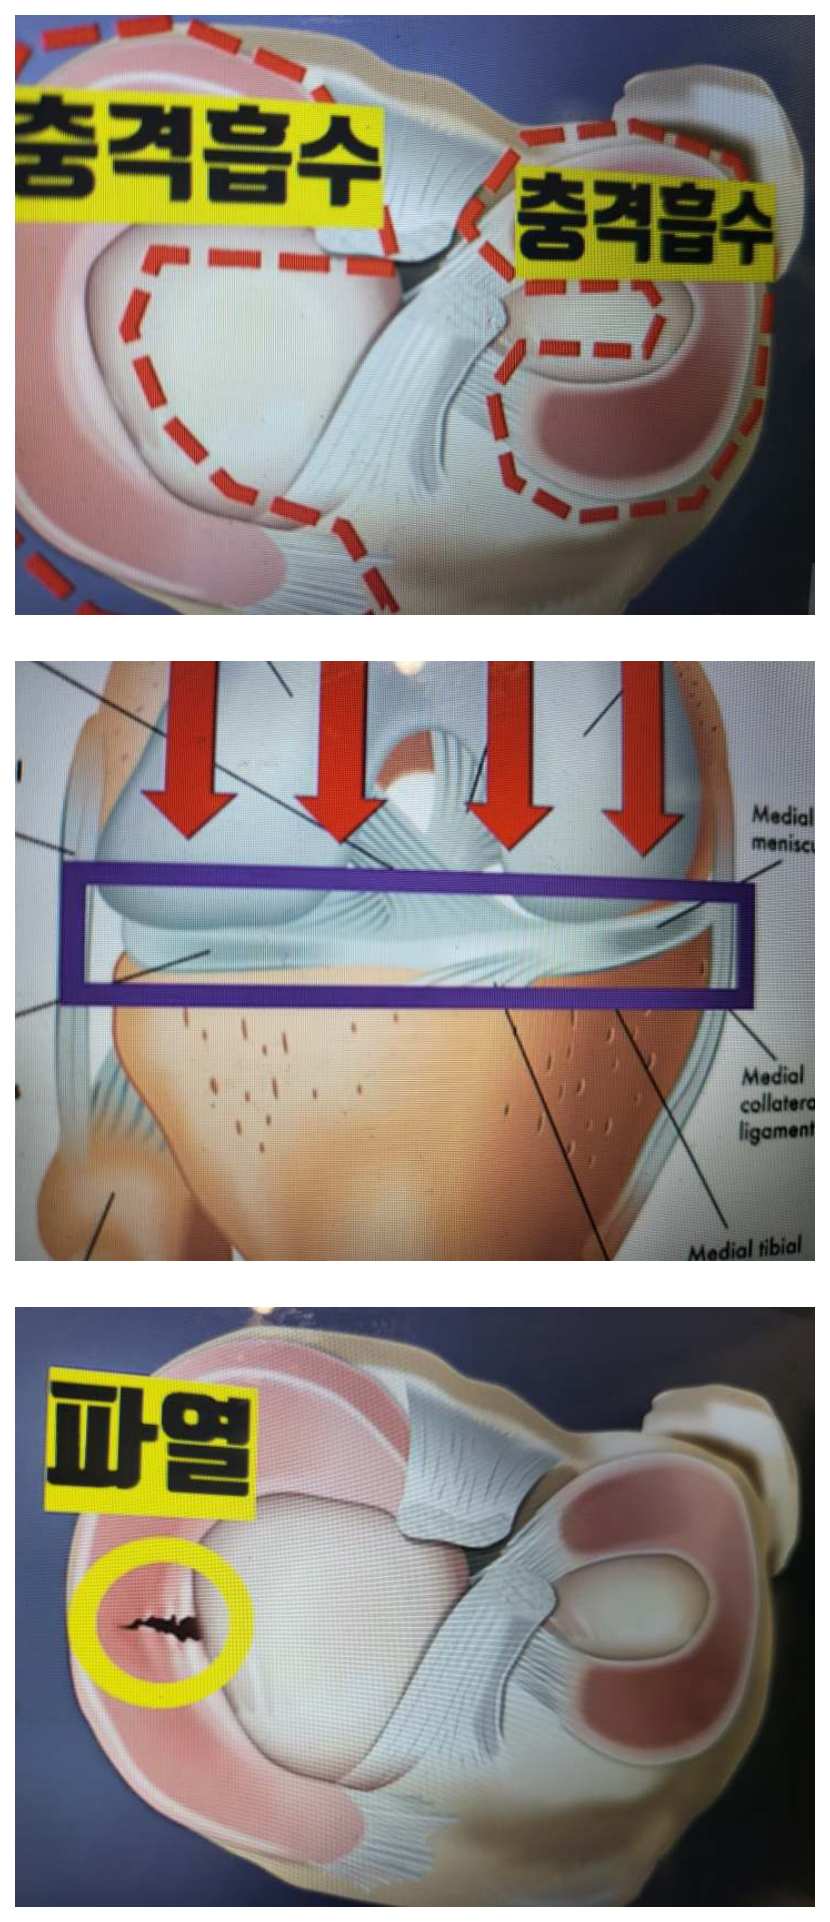

📌반월상 연골 사진 자료

우선 반월판 연골은 무릎 위의 관절과 아래 관절 사이에 있는 반달 형태의 연골로서 외측 반월판과 내측 반월판이 있습니다. 이 반월판 연골은 무릎 관절이 받는 외부 충격을 완화하여 무릎을 보호하는 역할을 하기에 신체에서 아주 중요한 역할을 합니다.

반월상 연골은 위에서 언급하였듯이 외부 충격을 완화해 주는 역할을 하는 만큼 손상되면 외부 충격을 그대로 받게 되기에 증상이 있기 마련인데 그 증상은 다음과 같습니다.

#무릎 연골 MRI사진

증상이 의심스러운 분이라면 정상 및 파열된 연골의 사진을 보면서 비교하고 이해하는 것은 필수입니다. 특히 MRI 사진 구하기 힘들 텐데 제가 첨부파일로 아래에 공유하겠습니다.